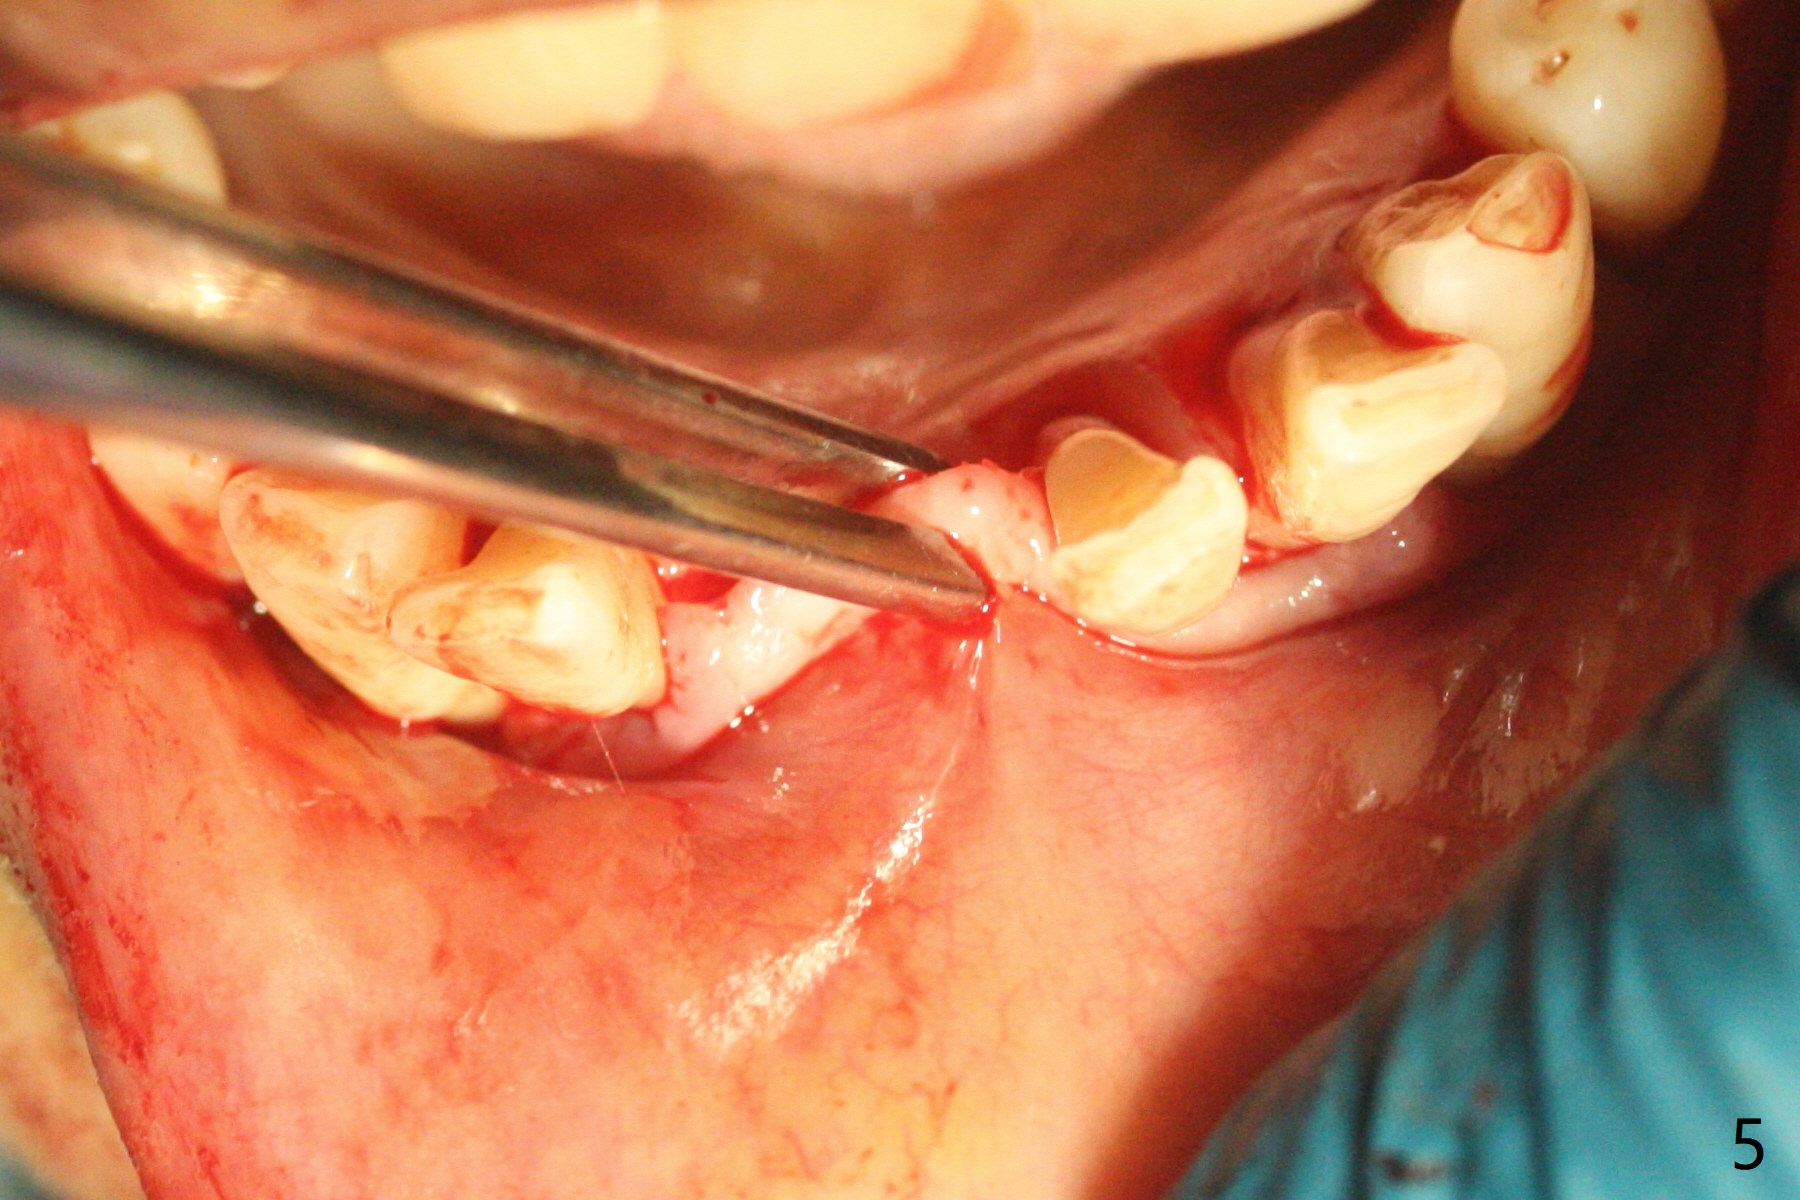

56岁女十分恐惧治疗,缺失右下1,其余切牙由于骨质吸收颊侧移位(图一:1,2),但是她不愿意拔除,同意右下1种植,牙周骨手术,植骨;植体整合后作为支抗,矫正移位下门牙。为了防止忘记舌侧瓣分离,先做舌侧切口(图二),然后颊侧瓣松弛分离(图三),包括使用前牙隧道刀(图四)切断颊侧骨膜,松弛到颊侧瓣能向舌侧牵拉3-4毫米(图五),舌侧瓣骨膜下广泛,深部分离(好像不能切断骨膜,图六),放置导板,磨平狭窄的牙槽嵴(图七:O(osteotomy)),植入2.5x12(4)毫米一段式植体(图八:故意舌侧植入,以便以后矫正),在颊侧骨板打多个出血洞(图八:箭头),然后把在平的器皿上形成的粘性骨板(sticky bone,图九),放置于植体和移位切牙周围(图十),接着使用消毒过的橡皮障punch(图十一(纸头相当于PRF膜;事先给助手示范))在三个PRF膜(图十二)打洞,套在植体和门牙上(图十三: 箭头),防止膜(图十四)和骨块(图十五,十六:*)移位,最后还必须使用最原始方法牙周敷料保护伤口(图十七)。术后9天,舌侧牙周敷料脱落,伤口稍微裂开(图十八)。术后18天撤除敷料,伤口裂开处有新鲜肉芽组织生长(图十九(*:下面是填入的骨粉,将是增宽的牙槽嵴(如果你是乐观主义者)),二十)。病人十分感激我们帮助她度过难关。她的确有sleep apnea,否定tongue thrust。术后三个月植体周围没有明显骨质吸收(图二十一至二十三),左下1,2轻度反合(图二十四),植体周围软组织健康(图二十五),5-5安置矫正器(图二十六,二十七,12 niti)。一周后下切牙向舌侧移动(图二十八),左下1,2反合纠正(图二十九)。再一周变化不大(图三十),植牙圈有些松动,两周后将重做临时牙冠,槽往舌侧移动。结果病人提前回来,植牙槽舌侧移位。一周后右下2不适(图三十一),尝试近中牵引(图三十二)。